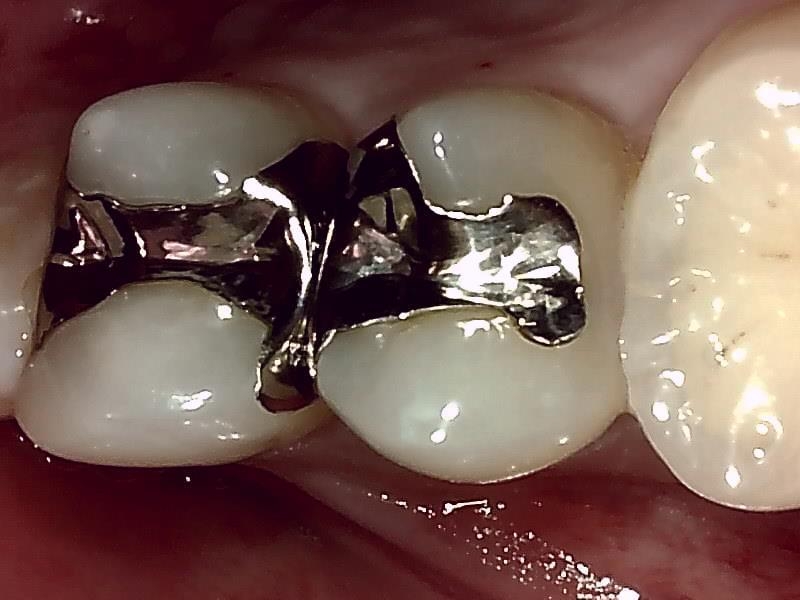

術前の咬合面の写真

不適合な金属の詰め物の除去。

インレー除去した写真